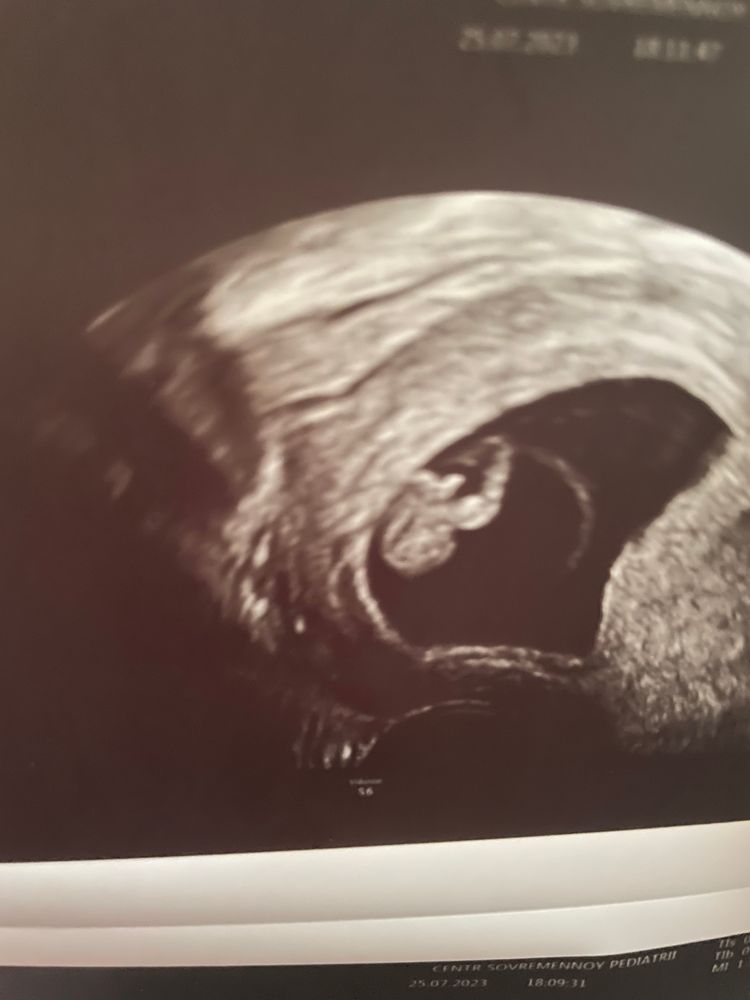

И сегодня в 10,4 же сделала экспериментальное узи у хорошего узиста и он почти со 100% сказал, что сомнений нет-мальчик. Показывал яички и писюн, я говорю разве может быть в 10 недель так четко видно, он-ну видите. Действительно картина была похожа. Фото, что он мне дал, вид снизу, прилагаю. Подскажите, разве кровь может ошибиться или откуда яйца и писюн в 10 недель🤦♀️

Оксана, ужас в том что я сама видела, между ног прям четко, но я то не специалист, я только причитала, разве может быть такого размера, может эта пуповина, он, нет- очевидно же всё это мальчик

Live, в 10 недель там все одинаково-половой бугорок.отличается только угол его наклона.

Я читала тут же на форуме, что до 16 недель пол могут определить не по явным половым признакам, а по углу отклонения их от плоскости "таза", так сказать. Еще в 12-13 недель снизу может торчать кобчик, более явно выраженный, чем у созревшего плода, а его за писюн принимают.